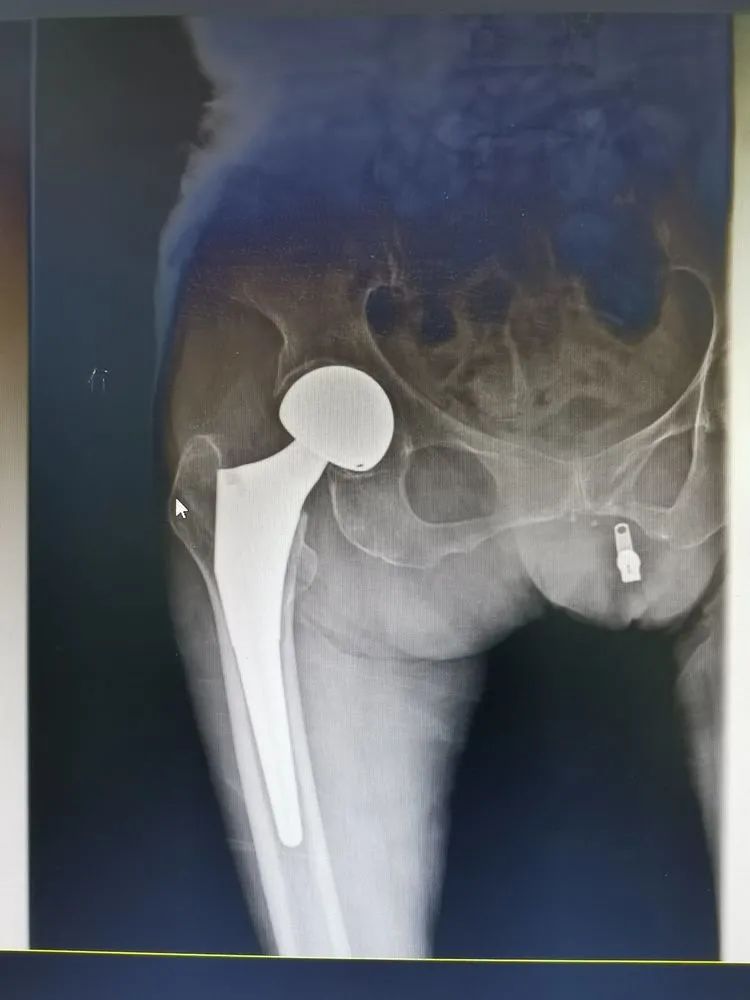

经过充分的术前准备,手术如期进行。手术室团队密切配合,麻醉科主任卜美林、副主任汪敏携手,一边安慰瘦弱的老人,一边熟练的从腰部棘突间的空隙进入,行腰硬联合麻醉,先为手术安全提供强大保障。集团骨科医疗中心总院副主任柏文昆主刀,王怀波主任配合,常规消毒、熟练入路.....柏主任手法娴熟,仅半小时不到,手术就顺利结束。术后,老人恢复良好,第二天就已经下床活动进行功能锻炼。